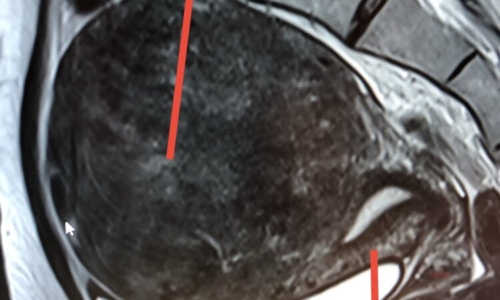

53 ADET MİYOM RAHİM KORUNARAK ÇIKARTILDI

RAHİM KORUYUCU MİYOM AMELİYATI Günümüzde, oldukça genç ve gelecekte çocuk istemi olan kadınlarda, çok büyük boyutlarda miyom görülmektedir.…